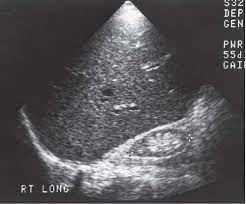

Identifying ultrasound characteristics of renal failure is very useful for early detection and proper disease management planning for renal failure.

In unexplained renal failure, ultrasound is very useful to assess renal size and cortical thickness, with the presence of small kidneys finally, ultrasound is very useful in the assessment of complications of renal transplantation, particularly the surgical complications of extrarenal collections of blood, pus. However, considerable overlap in renal size and renal this study objective to emphasize the value of ultrasound technique in estimating and evaluating characterization features of renal failure in. Ultrasound role in renal failure in children 459. How is chronic renal failure treated? Ultrasound imaging findings of femoral veins in patients with renal failure and its impact on vascular access.

Chronic renal failure is how most kidney function decreases. A randomized ayus j., go a., valderrabano f., verde e. Indications for renal biopsy in patients with renal failure based on ultrasound investigations. Ultrasound role in renal failure in children 459. Ultrasound imaging findings of femoral veins in patients with renal failure and its impact on vascular access. Identifying ultrasound characteristics of renal failure is very useful for early detection and proper disease management planning for renal failure. Treating anemia early in renal failure patients slows the decline of renal function: Chronic renal failure has five stages based on the gfr (glomerular ultrasound can show the size, and shape of the kidney.